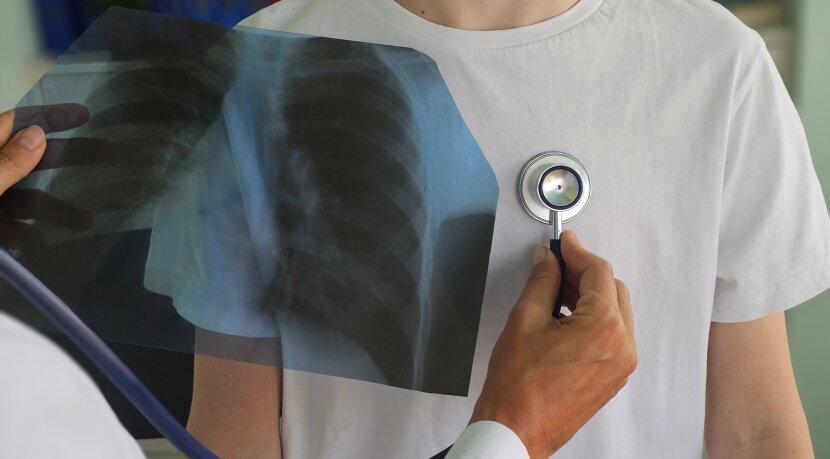

У День боротьби з туберкульозом лікар-фтизіопульмонолог, експерт Національного порталу з імунізації Оксана Молода відповіла на ключові питання про хворобу. Лікар нагадала, що за умови вчасної діагностики та безперервного лікування хвороби можна позбутися, а для її профілактики існує вакцинація.

За 9 місяців 2025 року було зареєстровано 11 614 випадків туберкульозу, серед дітей до 17 років — 408 випадків. Лідерами з захворюваності в Україні є Одеська, Кіровоградська, Дніпропетровська, Житомирська та Закарпатська області, що зумовлено, в першу чергу, міграційними процесами. Спостерігається зниження показника захворюваності на туберкульоз у порівнянні з 2024 роком на 18,2%.

Зверніться до лікаря, якщо кашель триває понад два тижні, тримається температура 37.2–38°C, ви без причин втратили понад 3 кг за місяць або відчуваєте постійну слабкість. Також обстеження обов’язкове після контакту з хворим на туберкульоз.